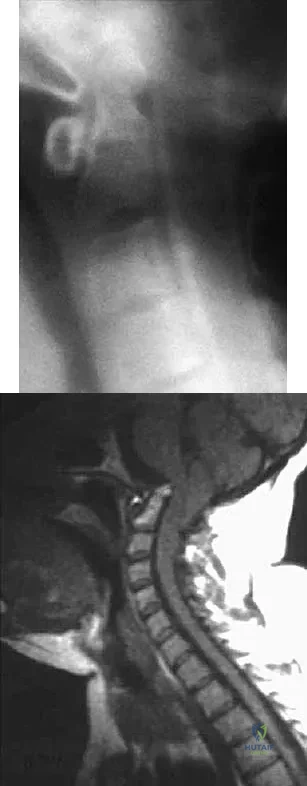

A 60-year-old woman with a history of breast cancer has progressive paraparesis. The MRI scan is shown in Figure 28. What form of management is most likely to restore or maintain ambulation?

Options:

- Radiation therapy and a thoracolumbosacral orthosis

- Laminectomy alone

- Laminectomy and radiation therapy

- Laminectomy and posterior fusion

- Anterior decompression and stabilization

Correct Answer: Anterior decompression and stabilization

Explanation:

Surgical decompression and stabilization have been shown to be the most effective means of improving neurologic function. Decompression is most reliably done from the side of the compression, which is anterior in this patient. Harrington KD: Metastatic tumors of the spine: Diagnosis and treatment. J Am Acad Orthop Surg 1993;1:76-86.